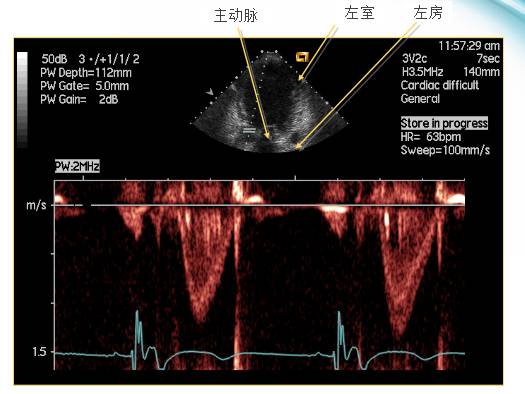

– 二尖瓣血流多普勒超声心动图

●超声心动图能测量每个时限的血流。P波是A波的前奏电信号,QRS波是主动脉血流的前奏电信号。

●E波: 心室舒张时的被动充盈。A波: 心房收缩期心室的主动充盈。

二尖瓣血流多普勒方法的观察过程

●程控SAV或PAV短于自身PR间期

●记录下E峰和A峰

●缩短SAV或PAV 20ms直到A峰被切

●延长SAV或PAV 10ms直到A峰完整